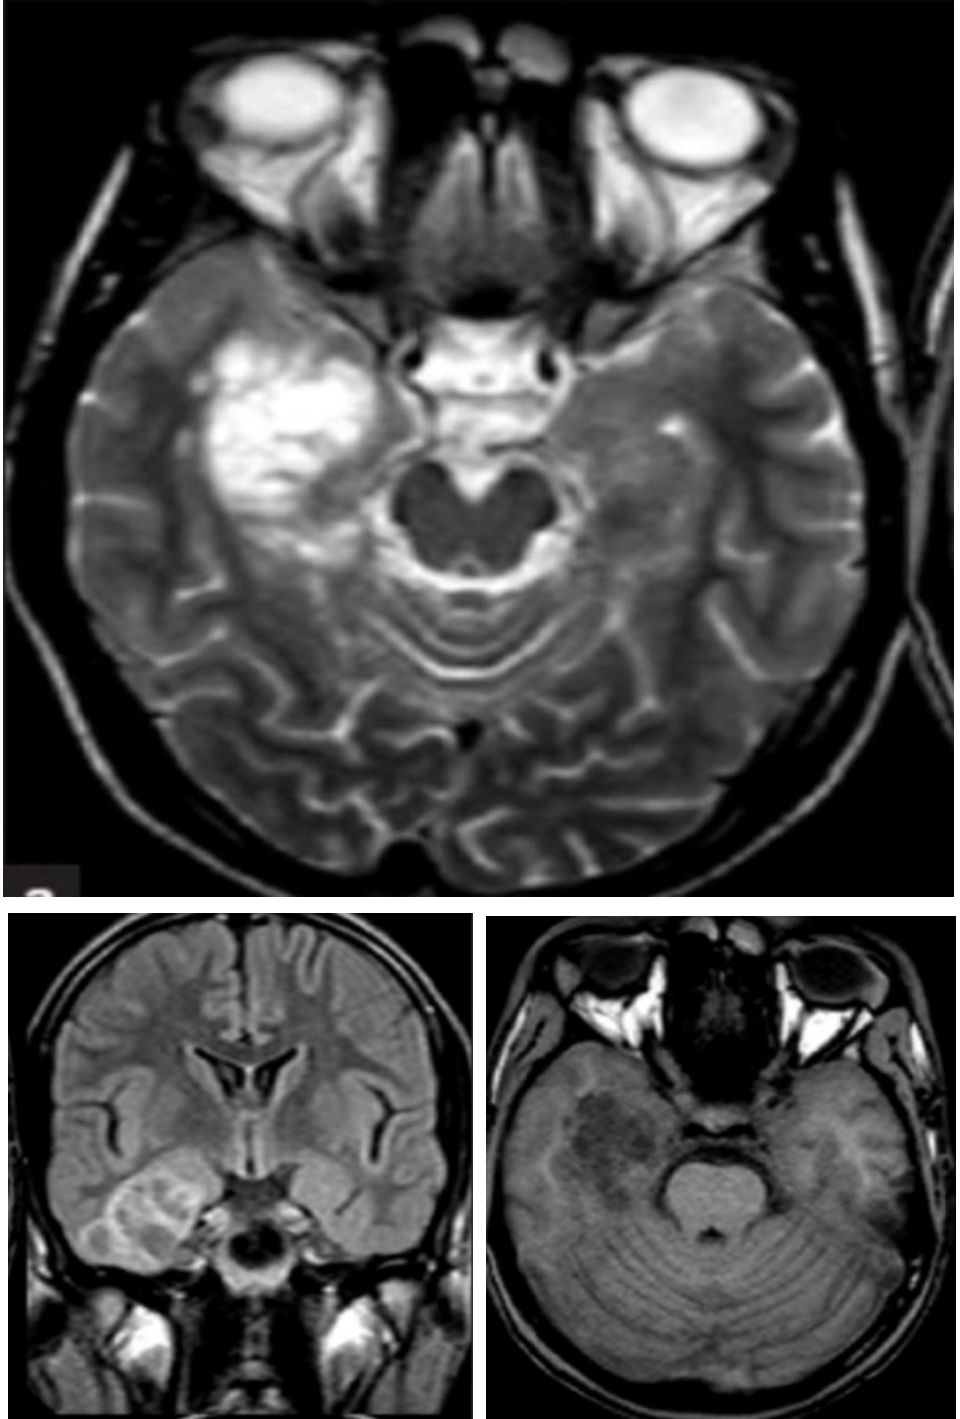

➤脑干胡椒粉改变: